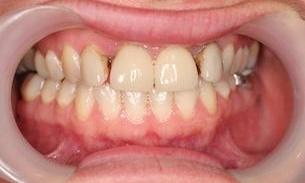

This gallery highlights the treatment of a patient who previously had braces but required additional restoration to close residual gaps. A Maryland cantilever bridge was placed to fill in these spaces, improving both dental function and aesthetics.